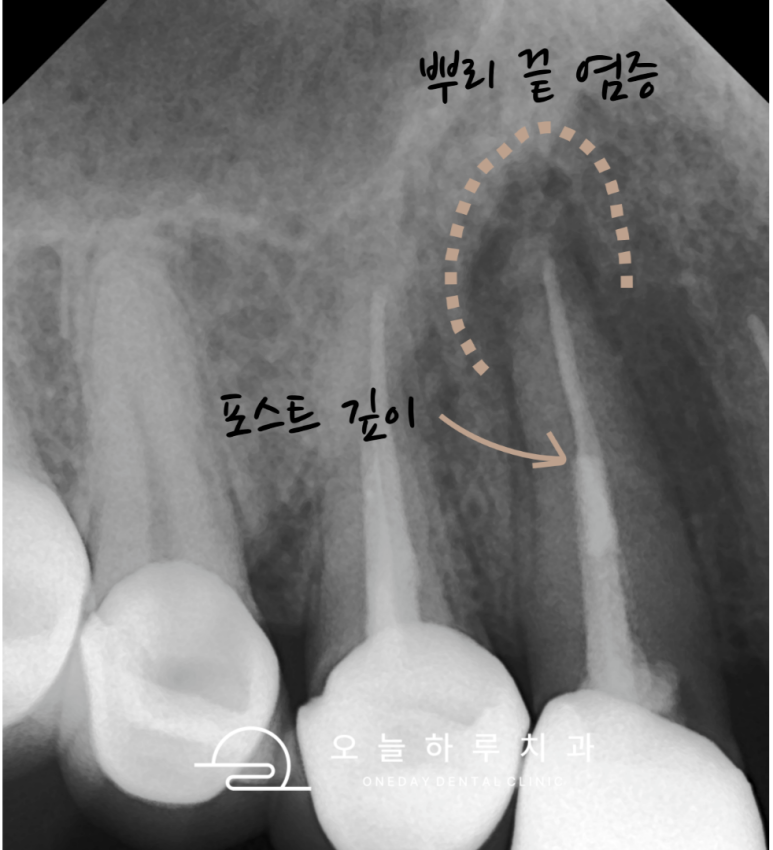

엑스레이를 통해 확인해보니

뿌리 끝에 큰 염증이 형성되어 있었고,

**포스트(post)**가 깊숙이 삽입되어 있었습니다.

🔍 고름이 자연스럽게 배출되면 통증은 없을 수 있으나,

염증은 내부에서 계속 진행되고 있기 때문에

반드시 치료가 필요합니다.